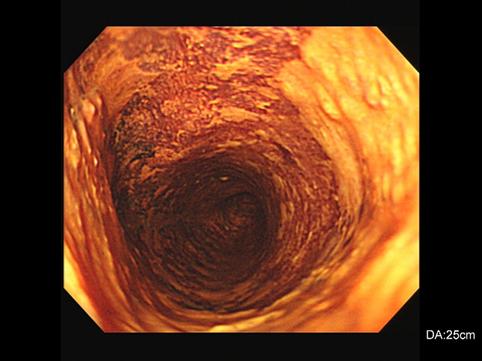

질환(병리주체)의 분류 악성 상피성종양/편평상피암

부위(장기별) 식도/중

검사방법 내시경

종양의 육안분류 0형(표재형)/IIc형(IIc)

종양의 최대경(밀리미터) 40이상

종양의 심달도 m